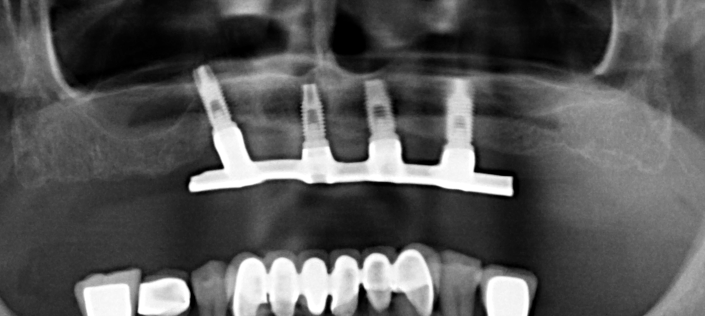

Hola, nos ha entrado este caso para volver a rehabilitarlo y el paciente no tiene nada de información de los implantes. Necesitamos saber todo lo necesaria de todos los implantes [...]

Buenos días, Me pongo en contacto con ustedes porque necesitaría saber la marca y la conexión de los implantes de la ortopanomografia que adjunto a continuación para tomar una medida [...]